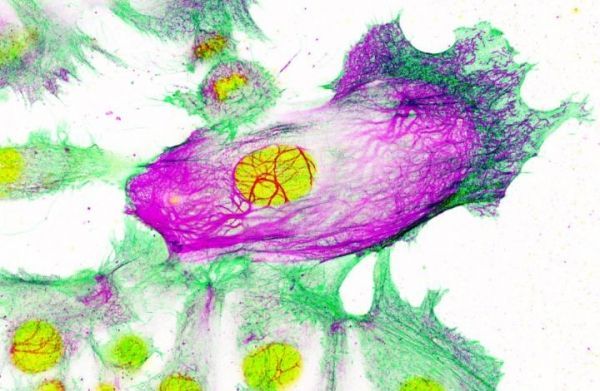

Image: Drug-resistant breast cancer cells surrounded by non-resistant cells. The cell nucleus is shown in yellow; while the cell's 'scaffolding' is shown in green and purple. Keratin-80 is shown in purple. (Credit: Imperial College London/Institute of Cancer Research)